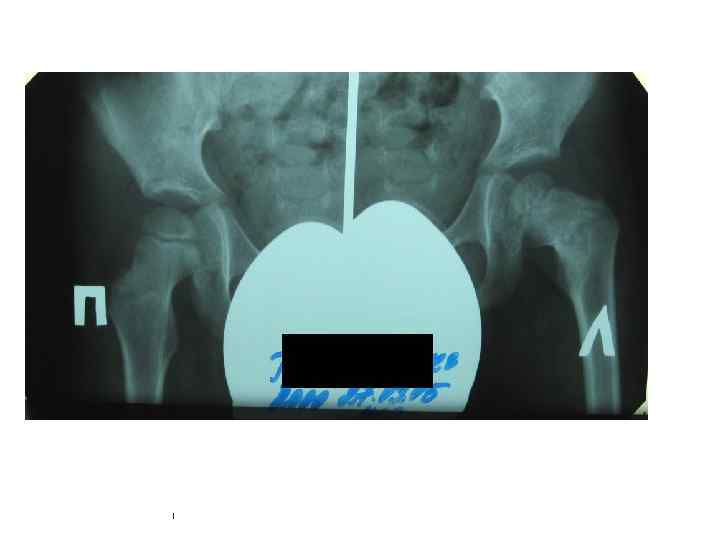

Туберкулезный коксит • Туберкулёз правого тазобедренного сустава. Секвестры тела подвздошной и головки бедренной костей, скопление экссудата в полости сустава и образование параартикулярного абсцесса. • рентгенограмма; • компьютерная томограмма; • магнитно-резонансная томограмма.